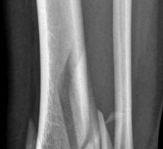

Tibial shaft fracture extending into the plafond—plate fixation Case description A 26-year-old man fell from …